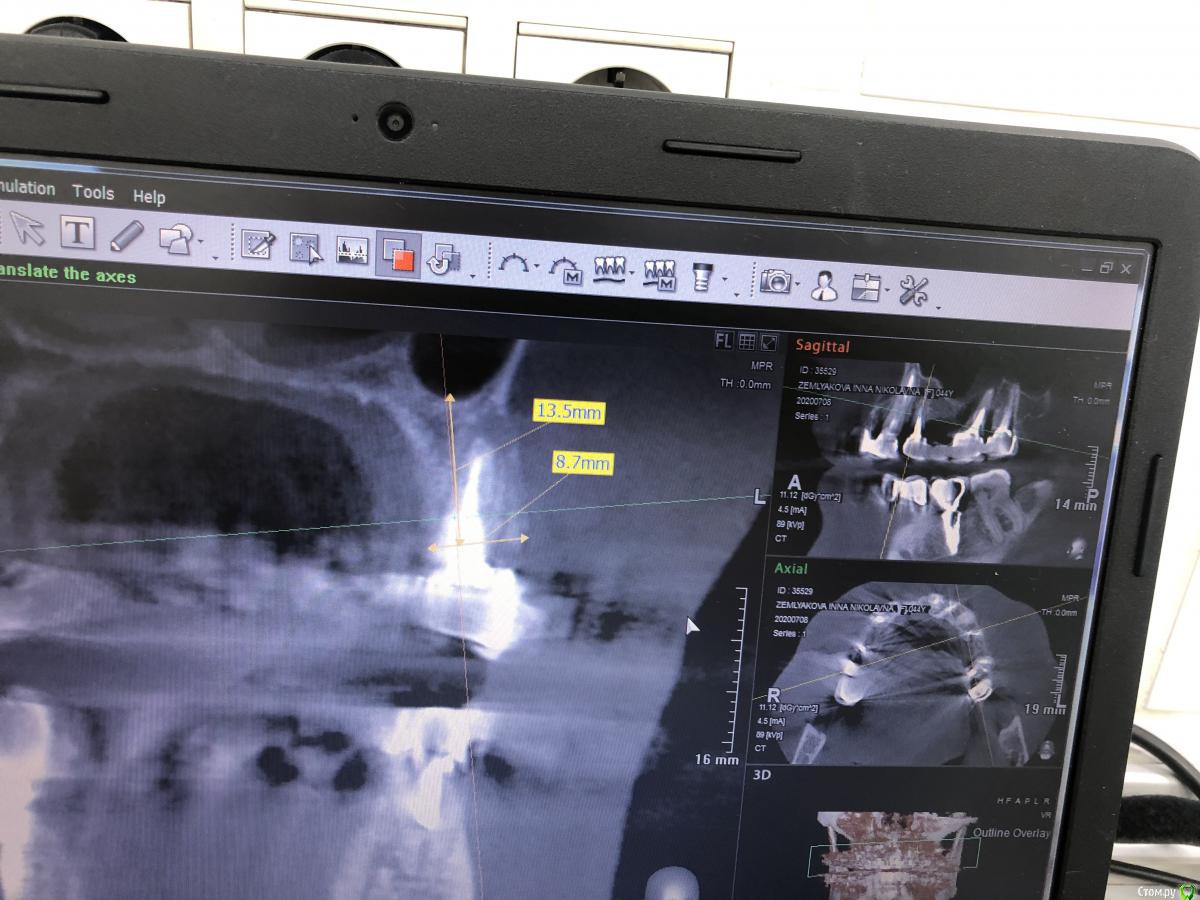

Александр07 Опубликовано 14 августа, 2020 Автор Поделиться Опубликовано 14 августа, 2020 Коллеги планируется имплантация на вч-удаление 2.4,2.6, 2.7 под ? ( ферула нет после снятие мк, можно попробовать удлинить но ортопед не особо настроен ) , здесь сложность в том что пац не может ходить без зубов, чтобы окружающие не знали об этом, Первый вариант это удаление 2.4-2.6 и капа , второй вариант это убрать 2.4,26.2,7 и импл с нагрузкой 2.4,2.5, 2.7 Вот срезы, скажите что думаете , насколько вероятно нагрузить и стоит ли, в обл 2.5 по хорошему откр с лифт, можно попробовать закрытый, 2.7 придётся смещать к перегородке межзубной Ссылка на комментарий